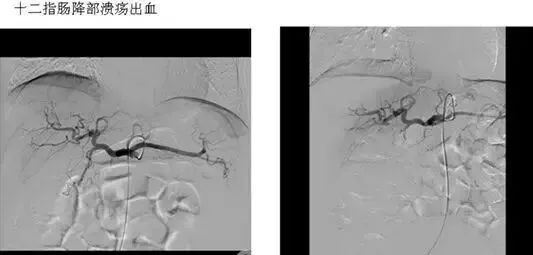

五、出血性疾病:鼻腔大出血、咯血、上消化道大出血、经皮肾镜术后出血、膀胱出血、产后出血等